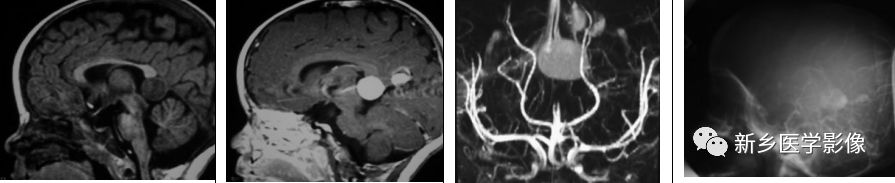

Galen静脉血管瘤

Galen静脉畸形是脉络膜型动静脉畸形,累及Galen静脉。它是动脉瘤引起动静脉血液分流的结果。其发生于胎龄6〜11周,表现为持续性胚胎前脑Markowski静脉。Galen静脉畸形其实是一个用词不当。Markowski静脉实际上注入Galen静脉。(注:Galen静脉动脉瘤样畸形,可分为真性Galen静脉动脉瘤样畸形(VGAMs)和继发性动脉瘤样扩张(VGGDs),VGAMs发生与血管胚胎发育异常关系密切,可分为壁型和脉络膜型,VGADs多为继发性改变,常伴有下游引流途径梗阻,确诊有赖于DSA造影)

矢状位T1WI示松果体区低信号肿块,矢状位及T1WI+C示病灶明显强化,MRA示Galen静脉畸形,脑血管灶影侧位示一隐约填充的Galen畸形静脉。